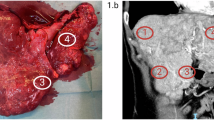

Symptomatic HAVMs, manifested mainly by cardiac failure or portal hypertension, were only reported in HHT2 patients (7.6%). Liver involvement was more frequently detected, by echodoppler screening, in HHT2 patients (57.6 vs. 43.5%), although the difference did not achieve significance. Anamnestic data revealed that liver involvement was present in the family of HHT2 patients but was not reported in relatives of HHT1 patients (61 vs. 0%, P < 0.001).

A significantly higher occurrence of HAVMs in HHT2 patients was suggested by two recent studies.27,29 In both cases the authors did not screen for HAVMs routinely but on the basis of clinical symptoms and signs such as a hepatic bruit on auscultation, heart failure, abdominal pain or elevated hepatic enzymes. We found patients with symptomatic hepatic involvement only in the HHT2 group. In our 10 years of experience in the Lyon center, 100% (n = 10) of the HHT patients who underwent hepatic transplantation were found to have a mutation in ACVRL1 (unpublished data), in accordance with a recent report.36 HAVMs are often family clustered in HHT2. When applying echodoppler screening in asymptomatic patients, the higher frequency of HAVMs in HHT2 did not achieve significance. Surprisingly, the echodoppler features of liver involvement were present in 57.6% of the HHT2 group but also 43% of the HHT1 group, which is higher than previously reported.10 These findings contrast with the small number of patients presenting with severe consequences of liver involvement, such as cardiac failure, portal hypertension and biliary necrosis, suggesting that hepatic lesions seen by echodoppler may remain silent in the majority of patients for many years, perhaps for life.12,37 There is a need for longitudinal survey of these patients to improve our understanding of the natural history of HAVMs since their complications are life-threatening.